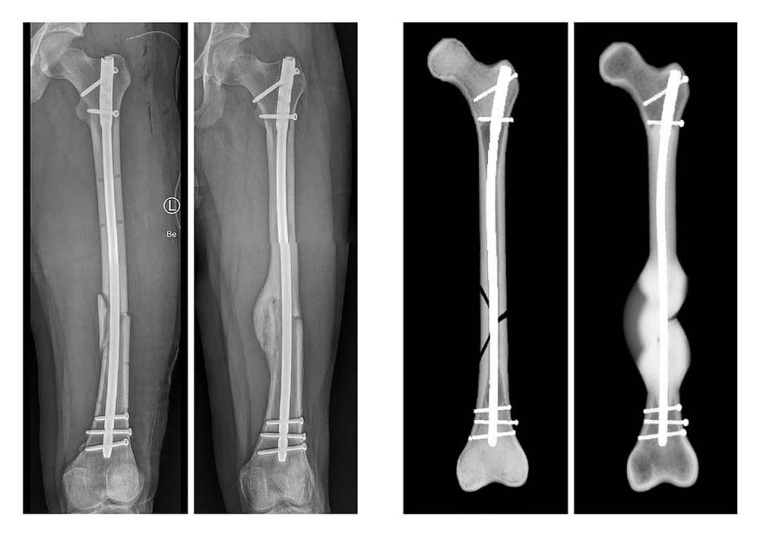

Für die Simulation wurden die klinischen Daten von 36 Patienten rückblickend analysiert. Diese hatten sich einen Schaftbruch des Oberschenkelknochens zugezogen, der durch die Implantation von Marknägeln versorgt worden war. Mithilfe von postoperativen Daten konnte die Computersimulation das Heilungsergebnis von 30 Fällen korrekt vorhersagen. „Bisherige Studien zum Ulmer Frakturheilungsmodell basierten auf Daten aus Tierversuchen oder aus Versuchen unter Laborbedingungen. Die Kooperation mit dem UKU hat es uns nun ermöglicht, das Heilungsmodell erstmalig mit klinischen Daten zu testen. So konnten wir den Prototypen des Softwaretools weiterentwickeln“, sagt Dr. Lucas Engelhardt von OSORA. „Das Heilungsmodell ist nicht nur in der Lage, Informationen zu erfolgreichen Heilungsverläufen zu generieren. Es wird ebenso zukünftig möglich sein, das Risiko für Komplikationen bis hin zu Pseudoarthrosen – also knöchernen Fehlheilungen – zu kalkulieren“, ergänzt Dr. Frank Niemeyer, ebenfalls von OSORA. Unter Berücksichtigung von patientenindividuellen Parametern, wie Größe und Gewicht, und Begleiterkrankungen, wie Osteoporose oder Adipositas, können dann Behandlungswege für jeden Patienten und jede Patientin individuell erstellt werden. Die Simulation unterstützt so die ärztliche Expertise durch Informationen zur Belastungsfähigkeit des Knochens während der Heilung.

Lediglich in sechs Fällen – von denen zwei Knochenbrüche geheilt und vier nicht geheilt waren – war die Prognose der Computersimulation nicht korrekt. „Jeder Patient heilt anders, jede Fraktur hat ihre Besonderheiten. Wir können aus den Daten ableiten, warum die Simulation in diesen Fällen nicht den realen Frakturheilungsverlauf abbildet, um neben der Biomechanik weitere Einflüsse auf das Knochenwachstum im Modell mit zu berücksichtigen. Diese Informationen sind für die weitere Entwicklung unserer Softwareplattform von größter Bedeutung, um die Präzision der Vorhersage kontinuierlich zu erhöhen“, erklärt Dr. Lucas Engelhardt.